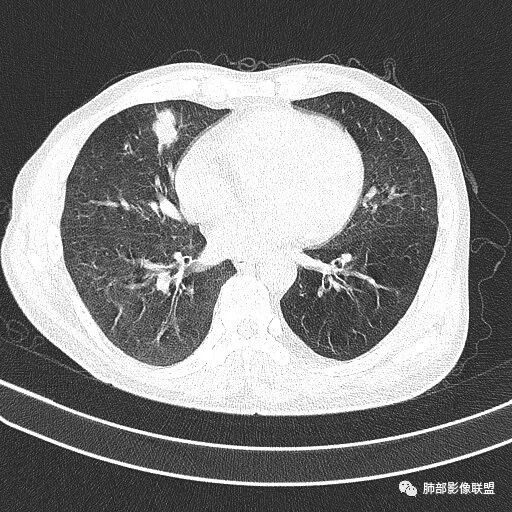

晨读病例  患者老年男性,因腰腹部疼痛3周,排尿困难1周入院。查尿常规及C反应蛋白提示泌尿系感染。肿瘤标志物NSE、细胞角蛋白19片断稍升高。胸部CT:右肺中叶内侧段类圆形肿块影,浅分叶,部分层面见深分叶,胸膜牵拉及支气管截断征象,边界清,密度低,无强化,且垮叶裂。综合考虑恶性病变,类癌及小细胞可能性大,鉴别囊肿等良性病变肺囊肿。

实性还是GGO?      实性

边界清楚、光滑?     光滑清楚,浅分叶,无明显毛刺

与支气管关系如何?   能看清楚吗

1.右肺中叶孤立不规则块影,浅分叶,未见液化或钙化,未见毛刺,未见脐凹,未见明显胸膜牵拉。

2.近肺门侧隐约见支气管截止。

3.外侧可见血管进入,病灶局部轻度强化。

上述均不符合光滑类圆形的支气管肺囊肿,也不符合典型的类癌,切不可先入为主。也不符合转移瘤。